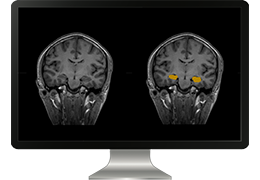

ART-Plan™ Artificial Intelligence Contouring